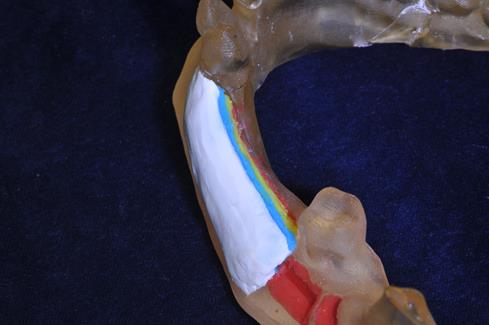

Рекомендуемые инструменты для забора аутокости KOHLER - смотрите на сайте medrmo.ru (Рис.5)  4. Послойное покрытие аутокости композиционными материалами: На первом этапе аутокость укрывают материалом «ОСТЕОМАТРИКС» (Рис.6)

4. Послойное покрытие аутокости композиционными материалами: На первом этапе аутокость укрывают материалом «ОСТЕОМАТРИКС» (Рис.6)  Это биокомпозиционный материал, который состоит из нативного гидроксиаппатита (75%), костного коллагена (25%) и костных сульфатированных гликозаминогликанов. Костный коллаген в его составе способен избирательно сорбировать тромбоциты крови, формируя фиксированную тромбоцитарную массу на имплантируемом материале, и, в конечном итоге, обеспечивать высвобождение большого количества факторов роста (Рис.7)

Это биокомпозиционный материал, который состоит из нативного гидроксиаппатита (75%), костного коллагена (25%) и костных сульфатированных гликозаминогликанов. Костный коллаген в его составе способен избирательно сорбировать тромбоциты крови, формируя фиксированную тромбоцитарную массу на имплантируемом материале, и, в конечном итоге, обеспечивать высвобождение большого количества факторов роста (Рис.7)  В то же время сульфатированные гликозаминогликаны (сГАГ) в составе материала могут непосредственно участвовать в активации остеонеогенеза, оказывая влияние на многие показатели обмена соединительной ткани, в частности, стимулируя размножение и дифференцировку её клеток (более подробно читайте здесь). Достигаемая цель - обеспечение индукции костеобразования в зоне имплантации за счет уникальных свойств материала «Остеоматрикс». На втором этапе «ОСТЕОМАТРИКС» покрывают остеокондуктивным материалом «БИОИМПЛАНТАТ ГАП» - это 100% гидроксиаппатит (Рис.8)

В то же время сульфатированные гликозаминогликаны (сГАГ) в составе материала могут непосредственно участвовать в активации остеонеогенеза, оказывая влияние на многие показатели обмена соединительной ткани, в частности, стимулируя размножение и дифференцировку её клеток (более подробно читайте здесь). Достигаемая цель - обеспечение индукции костеобразования в зоне имплантации за счет уникальных свойств материала «Остеоматрикс». На втором этапе «ОСТЕОМАТРИКС» покрывают остеокондуктивным материалом «БИОИМПЛАНТАТ ГАП» - это 100% гидроксиаппатит (Рис.8)  Покрытие материалом Биоимплант ГАП (Рис.9)

Покрытие материалом Биоимплант ГАП (Рис.9)  Кроме того, данный слой является основным барьером, препятствующим проникновению клеток слизистой в зону активации костеобразования и реализации ими своих способностей по растворению окружающих тканей. То есть является своеобразной «сыпучей», крайне медленно резорбируемой мембраной. (Более подробно см. "БИОИМПЛАНТАТ ГАП"). Рекомендуемые инструменты для внесения костных материалов KOHLER - читайте на сайте medrmo.ru (Рис.10)

Кроме того, данный слой является основным барьером, препятствующим проникновению клеток слизистой в зону активации костеобразования и реализации ими своих способностей по растворению окружающих тканей. То есть является своеобразной «сыпучей», крайне медленно резорбируемой мембраной. (Более подробно см. "БИОИМПЛАНТАТ ГАП"). Рекомендуемые инструменты для внесения костных материалов KOHLER - читайте на сайте medrmo.ru (Рис.10)  Цель – формирование и поддержание объема тканей в операционной зоне и создание границы между имплантатом и слизистой. 5. Покрытие аргументированного участка. В качестве последнего слоя используется коллагеновое покрытие «БИОМАТРИКС» - МЕМБРАНА (Рис.11)

Цель – формирование и поддержание объема тканей в операционной зоне и создание границы между имплантатом и слизистой. 5. Покрытие аргументированного участка. В качестве последнего слоя используется коллагеновое покрытие «БИОМАТРИКС» - МЕМБРАНА (Рис.11)  Покрытие мембраной Биоматрис. (Рис.12)

Мембрана Биоматрикс (Рис.13)  Применение коллагеновой мембраны препятствует миграции частиц материала за пределы операционной зоны и обеспечивает надёжную изоляцию на длительный период (1-2 месяца) послойного кластера от слизистой, что необходимо для ... (более подробно читайте «БИОМАТРИКС» - МЕМБРАНА). Послойный вид используемых материалов:

Применение коллагеновой мембраны препятствует миграции частиц материала за пределы операционной зоны и обеспечивает надёжную изоляцию на длительный период (1-2 месяца) послойного кластера от слизистой, что необходимо для ... (более подробно читайте «БИОМАТРИКС» - МЕМБРАНА). Послойный вид используемых материалов: